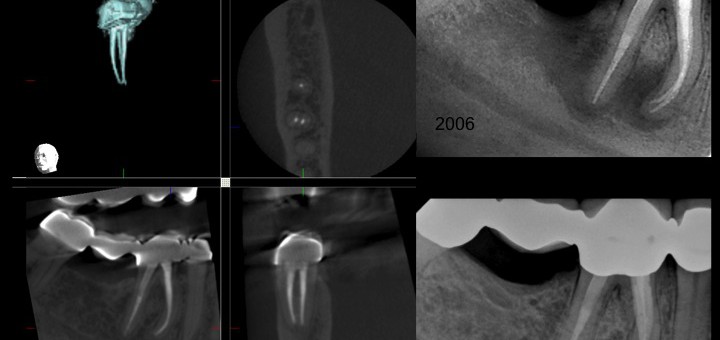

MCM Kategorie: 1_Behandlungsspektrum